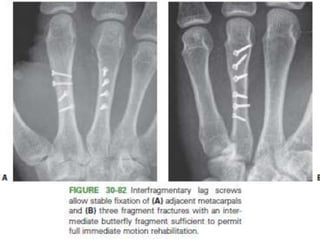

Open Reduction and Internal Fixation

• Indications :

– Intra-articular fractures that cannot be reduced

– multiple fractures without inherent stability

– open fractures especially when associated with tendon

disruptions.

• Internal fixation can be accomplished with

– intraosseous wiring,

– composite wiring,

– screws only, or

– Screws and plates